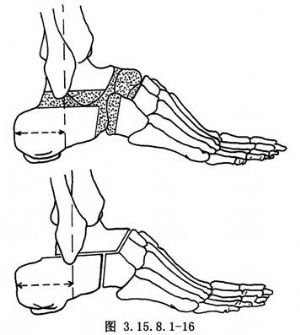

距下(距跟)、距舟、跟骰关节融合称三关节融合。虽是最早设计的方法,但目前这种方法仍然是最常使用的手术。手术原则旨在楔形切除距下关节纠正内翻,切除跟骰、距舟关节,纠正前足内收和内翻,楔形切除的底边方向相反,也可纠正足外展和外翻畸形。手术相关解剖见下图(图3.15.8.1-1,3.15.8.1-2)。

4.舟骨切除足向后移位,可加强足的稳定性(图3.15.8.1-16)。